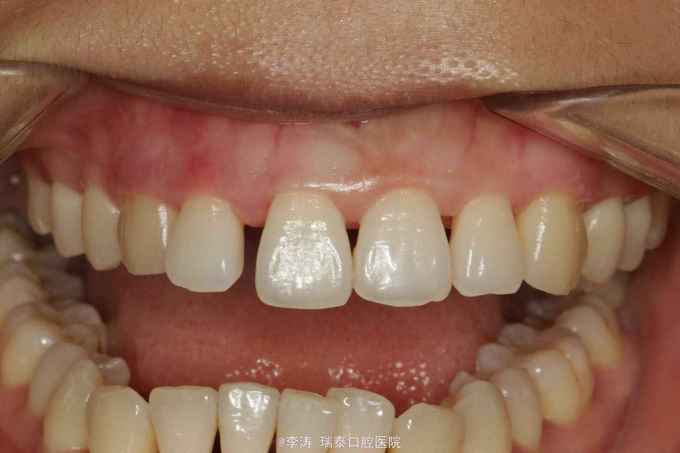

从症状和病史可诊断为急性牙周炎, 行全口洁治龈下刮治,牙周上盐酸米洛环素,一月后牙龈炎症消退,牙龈退缩使前牙可见明显间隙。

当发现牙齿出现缝隙时应该寻找原因,这么年轻出现牙周炎的概率还是比较小。 临外对前牙形成的间隙,不知道大家有什么办法关闭毕竟患者还太年轻